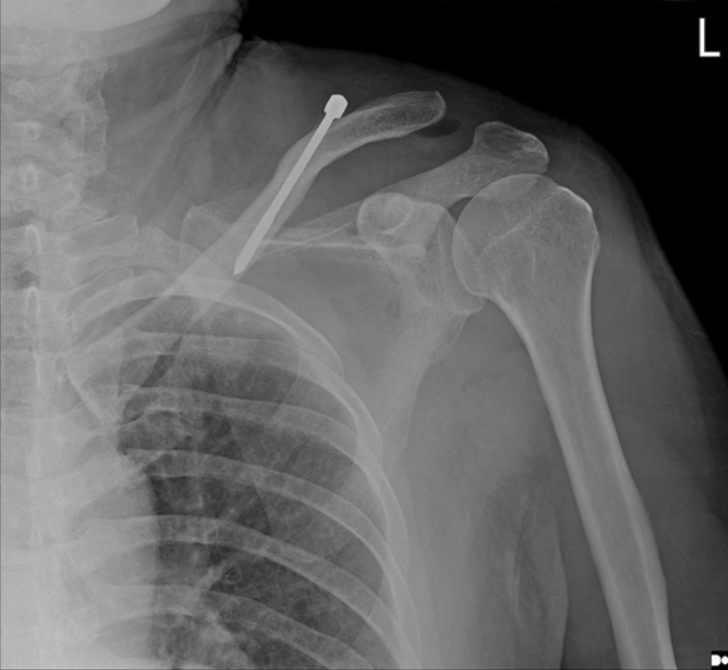

肩部正位平片显示锁骨中轴线状骨折,肩锁关节间隙无明显增宽,锁骨外侧端无明显增高

术后立即肩部x线片显示,锁骨骨折切开复位和Knowles针内固定后,肩锁关节(ACJ)明显移位。根据Rockwood分型诊断为V型ACJ脱位